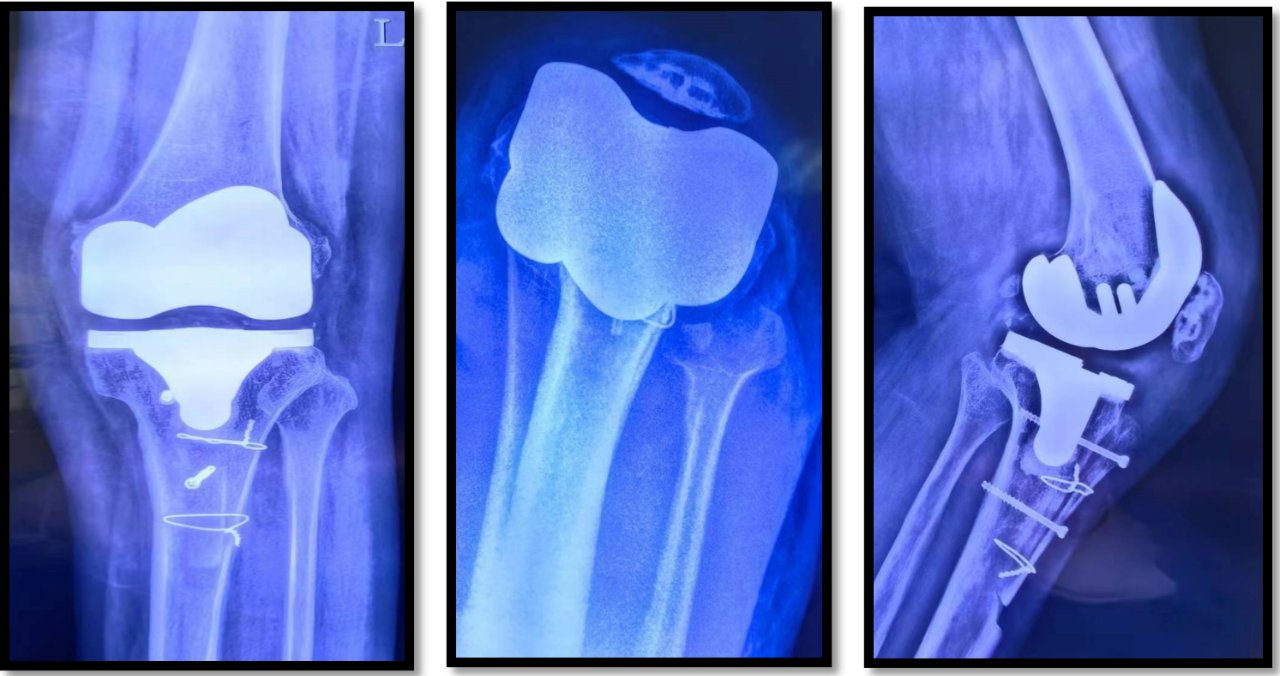

【影像学检查】

【诊断】左侧髌骨固定性脱位

【入院治疗方案】完善术前常规检查,准备择期手术治疗。